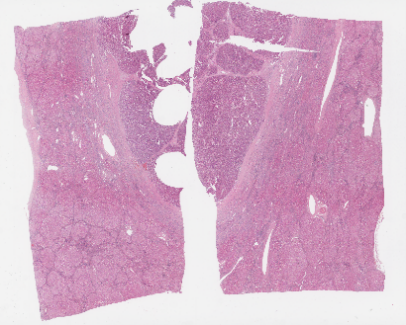

图1.原始病理图片